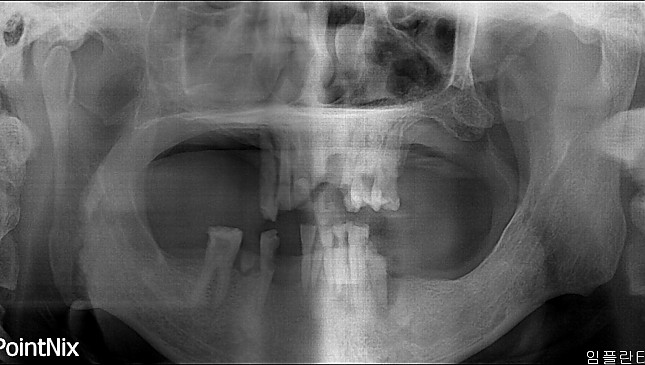

치아살리기 치료 전후 사진

고난이도 임플란트 치료 전후사진

잇몸 전체가 무너져 동시다발적으로 죽어가던 치아들을 한꺼번에 살려 냅니다.